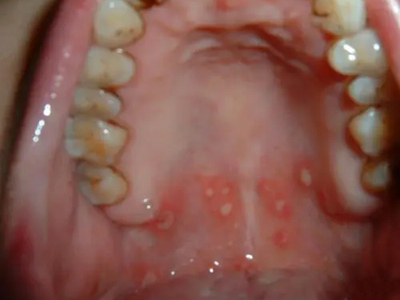

口腔

溃疡

溃疡性口炎嘴里有几个灰白色溃疡面图

溃疡性口炎患者口腔上方的位置,医学上称为上腭,局部出现溃疡后,表面覆盖薄厚不一的灰白色假膜,大小不等,独立或聚集存在,周围黏膜发红,多因金黄色葡萄球菌等细菌感染引起。